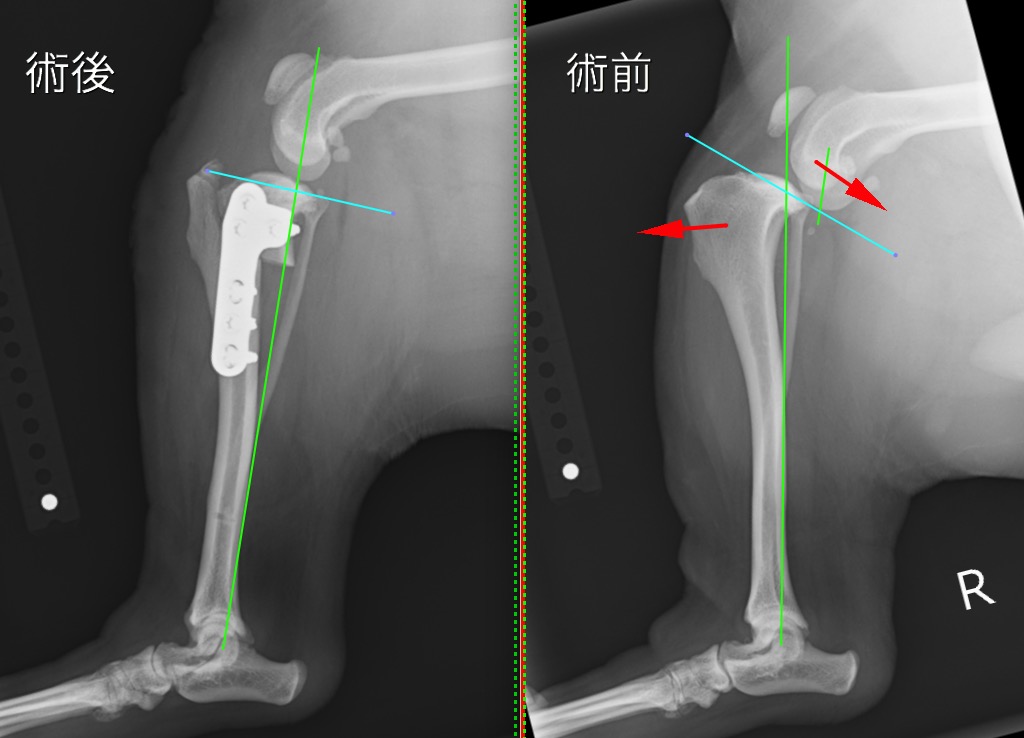

手術前後のX線写真を比較すると、術後は体重のかかる機能軸(緑線)に対して膝の中の傾斜(水色線)が垂直に近くなり、大腿骨と脛骨の連続性が回復しているのが分かります。